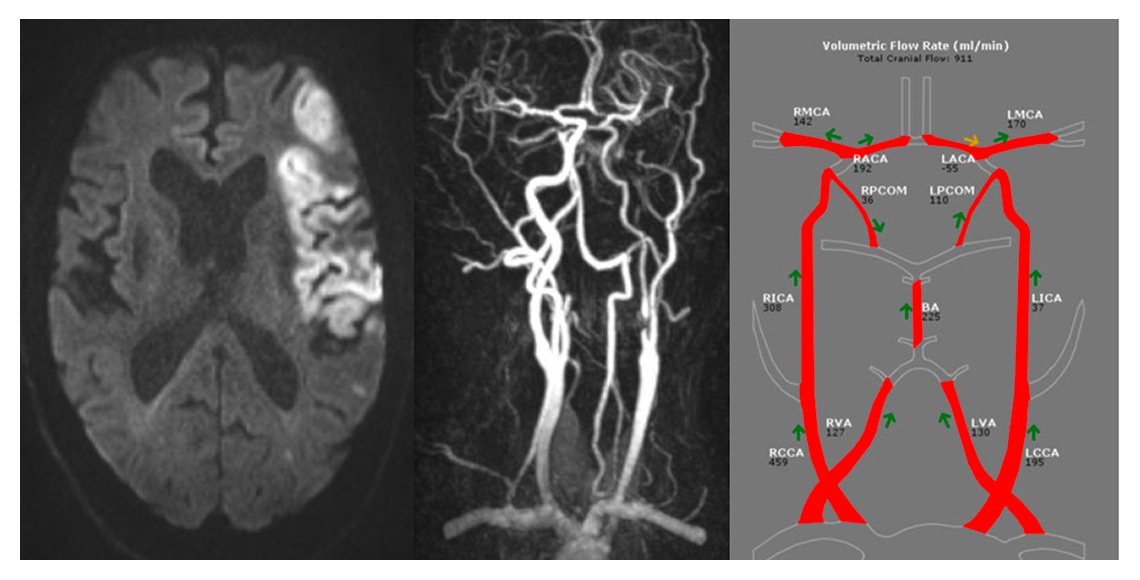

Figure 5

Illustrative case of a 61 year male patient with ischaemic stroke in the left MCA territory due to high grade stenosis of the left ICA with consecutive reversal of flow in the left ACA.

BA = basilar artery; LACA = left anterior cerebral artery; LCCA = left common carotid artery; LICA = left internal carotid artery; LMCA = left middle cerebral artery; LPCA = left posterior cerebral artery; LVA = left vertebral artery; RACA = right anterior cerebral artery; RCCA = right common carotid artery; RICA = right internal carotid artery; RMCA = right middle cerebral artery; RPCA = right posterior cerebral artery; RVA = right vertebral artery

Nineteen (9.1%) stenoses were identified in 17 patients, mostly (n = 16) extracranial (table 1). Ten stenoses were high-grade (ICA), eight moderate (ICA, VA, PCA and MCA), and one low grade (VA). An illustrative case with high-grade stenosis of the left ICA and consecutive reversal flow in the left ACA is shown in figure 5. In the case of stenosis of the ICA (n = 14), flow velocities (PSV and EDV) obtained by CCD were higher than with PC-MRA, albeit this was not significant. The correlations were moderate, with Spearman’s rho of 0.451 for PSV and 0.466 for EDV, both being not significant.